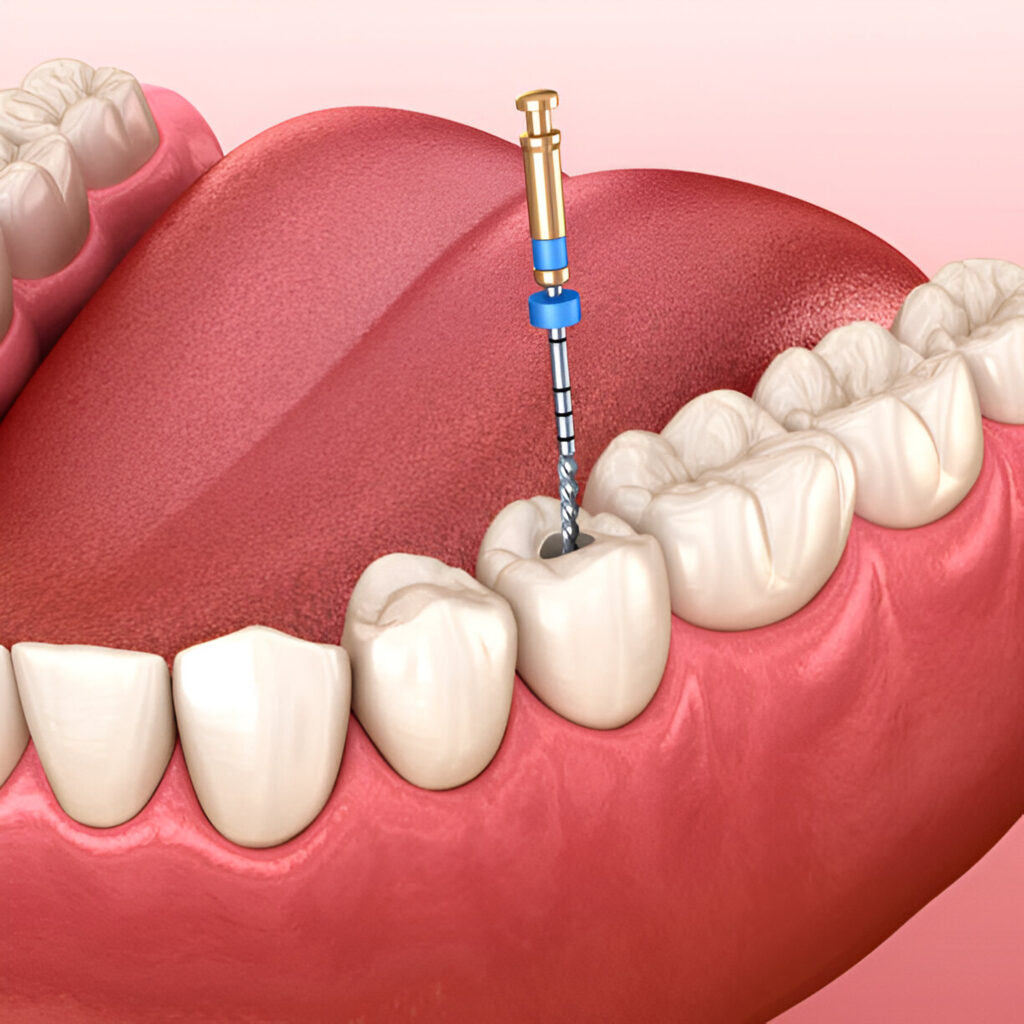

Root Canal Treatment

Surgical removal of nerves is referred to as root canal treatment. This method is used when a tooth is considered badly decayed or infected. Its process includes taking out the damaged nerve and pulp, cleaning the tooth's base, and sealing it.

What Is Root Canal Treatment?

Root canal treatment is a procedure to save a severely decayed or infected tooth by removing the damaged nerves and pulp. The tooth is then cleaned, sealed, and restored to preserve its function and prevent further infection.

Procedure

Local anesthesia is administered prior to undergoing the septic removal of infected pulp, cleaning and disinfecting of the tooth interior, capping and sealing it.